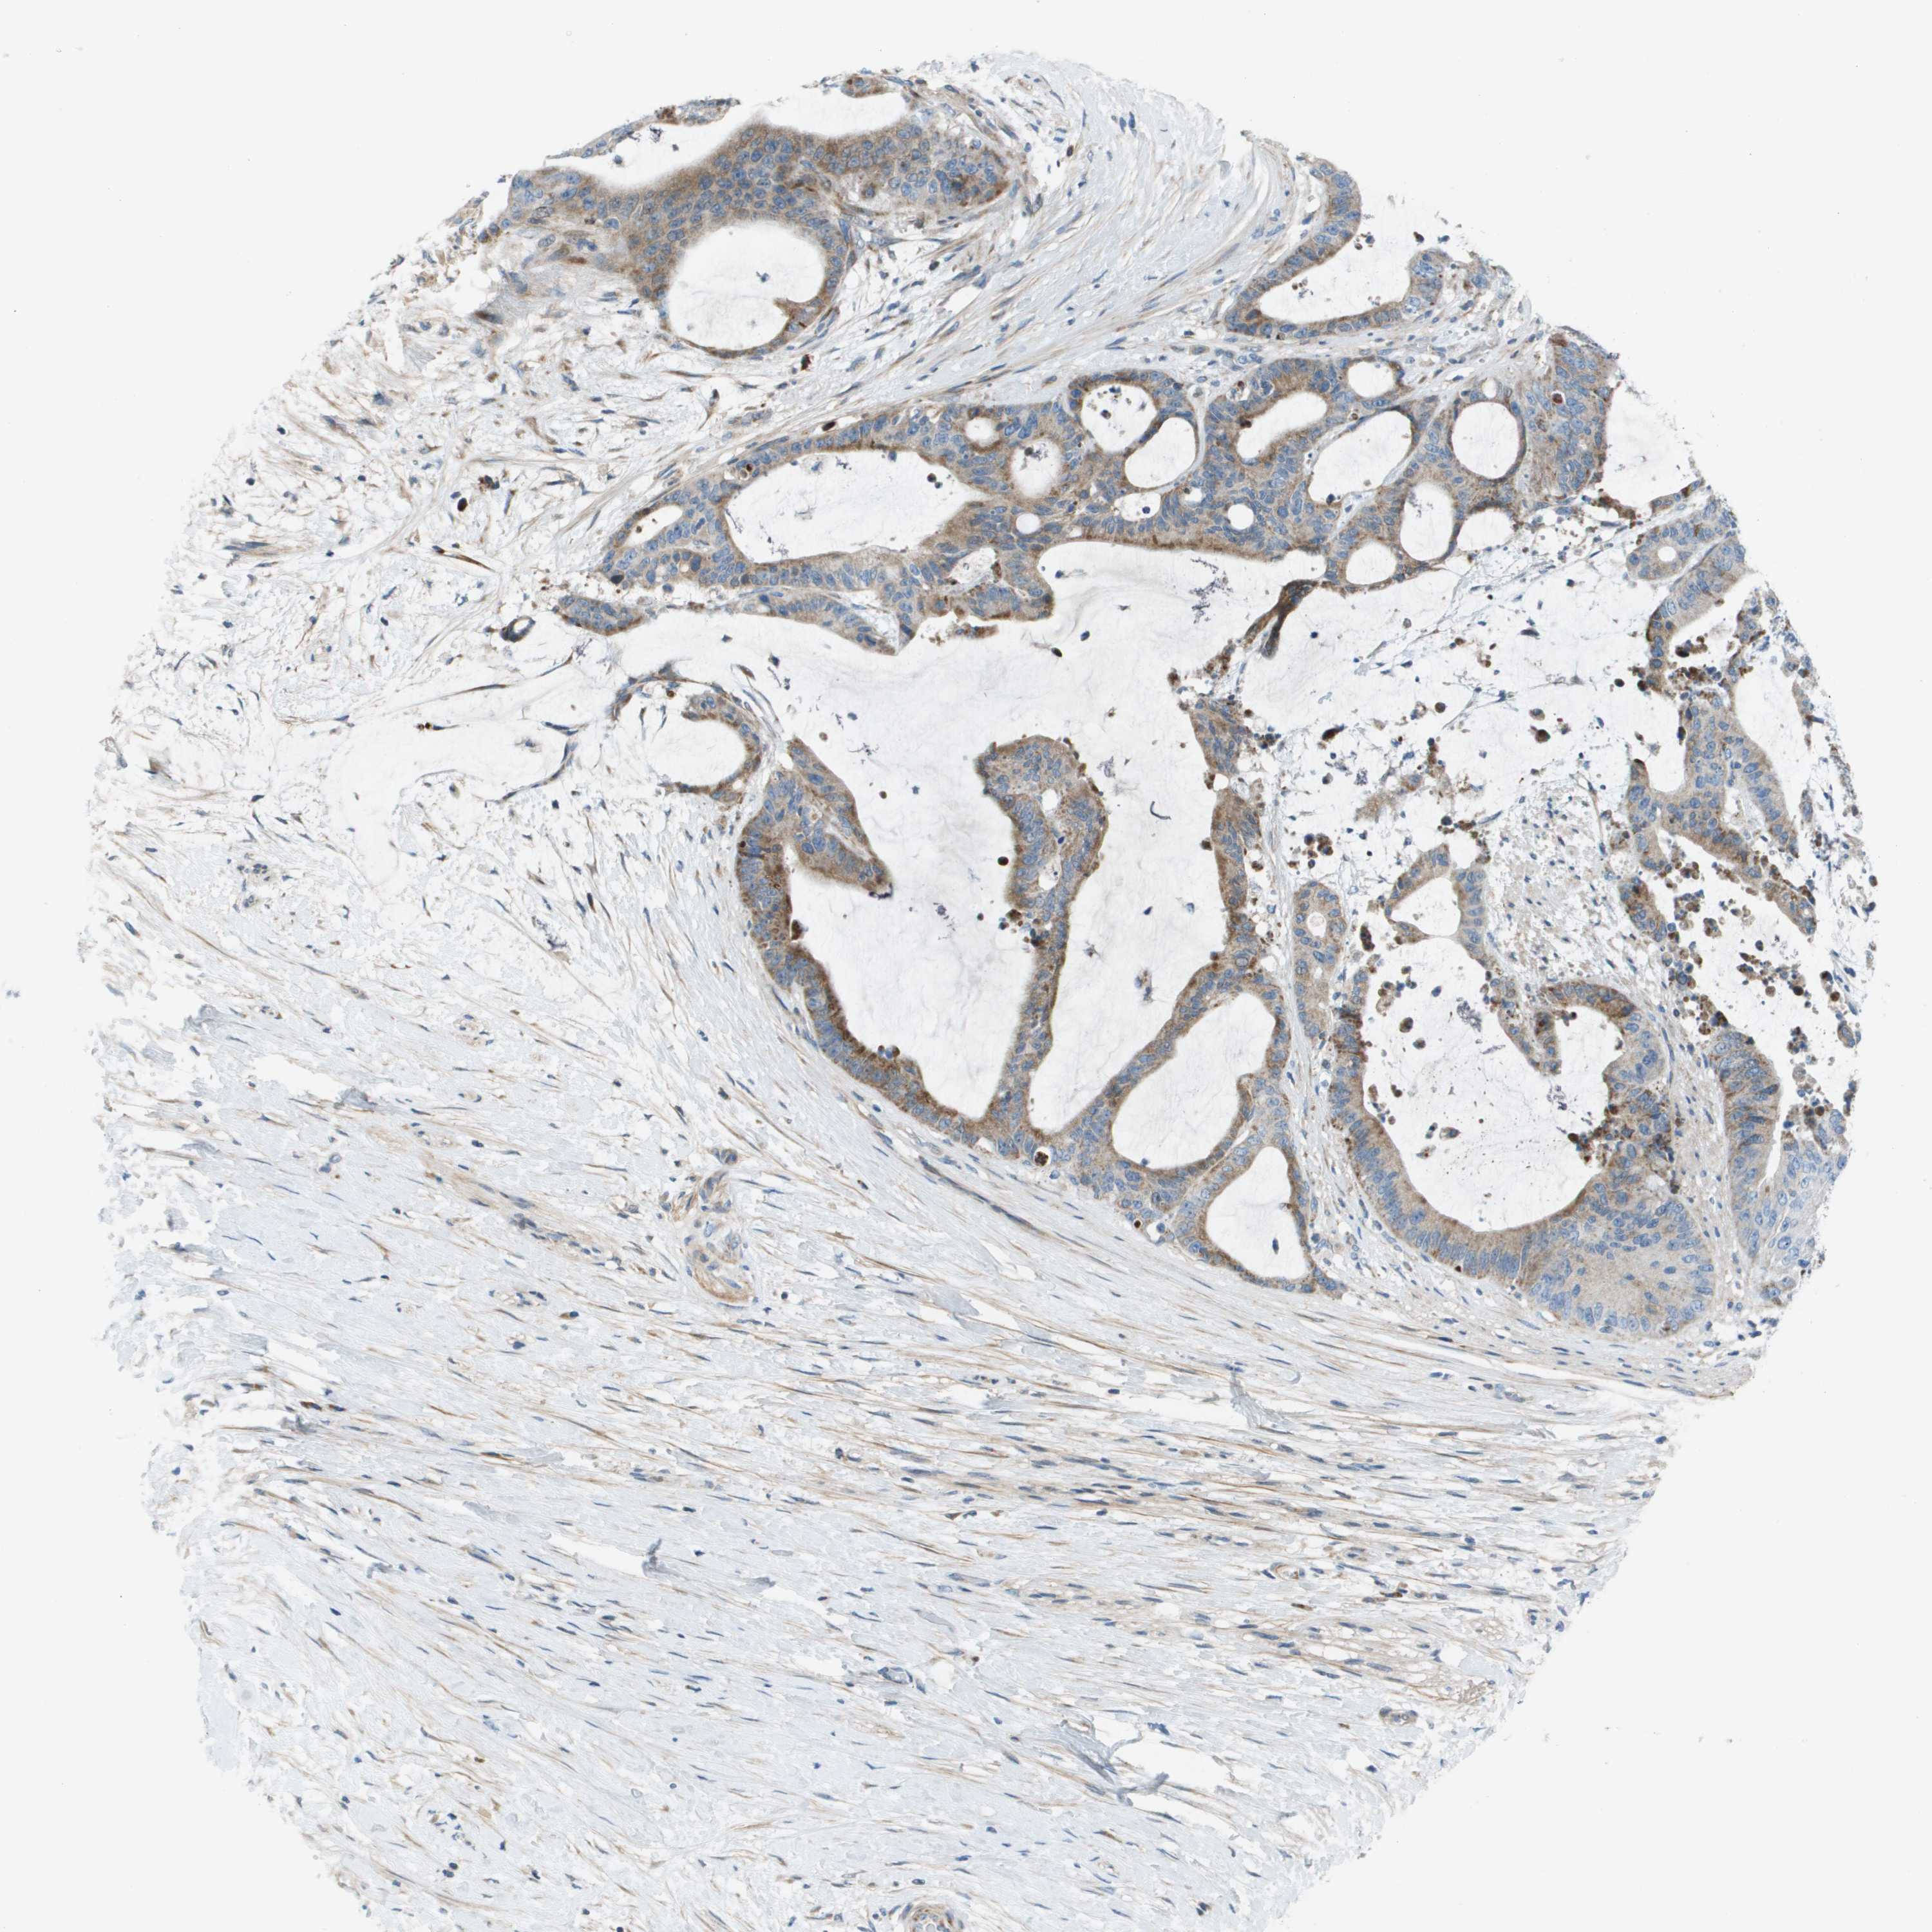

LIVER CANCER - Protein expressioni

A mouse-over function shows sample information and annotation data. Click on an image to view it in a full screen mode. Samples can be filtered based on level of antibody staining by selecting one or several of the following categories: high, medium, low and not detected. The assay and annotation is described here.

Note that samples used for immunohistochemistry by the Human Protein Atlas do not correspond to samples in the TCGA dataset.

Antibody stainingi

Antibody staining in the annotated cell types in the current human tissue is reported as not detected, low, medium, or high, based on conventional immunohistochemistry profiling in selected tissues. This score is based on the combination of the staining intensity and fraction of stained cells.

Each image is clickable and will lead to virtual microscopy that enables deeper exploration of all samples and also displays staining intensity scores, fraction scores and subcellular localization as well as patient and tissue information for each sample.

Antibody HPA011762

Antibody HPA017086

Staining

High

Medium

Low

Not detected

Intensity

Strong

Moderate

Weak

Negative

Quantity

>75%

75%-25%

<25%

None

Location

Nuclear

Cytoplasmic/membranous

Cytoplasmic/membranous,nuclear

Cholangiocarcinoma

Carcinoma, Hepatocellular, NOS